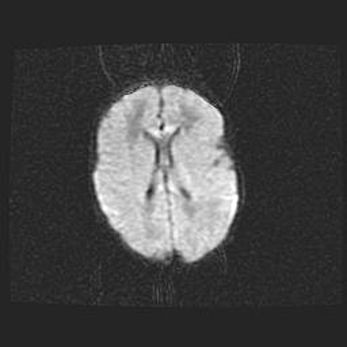

Множественные мелкие кисты перивентрикулярной области.

Киста прозрачной перегородки.

Возраст: 28 дней

Вес: 2400 г

Пол: женский

Окружность головы: 33 см

Срок гестации: 34 недели

Перивентрикулярная киста – это полостное образование в околожелудочковых областях белового вещества головного мозга. С морфологической точки зрения – это мелкоочаговая зона коагуляционного некроза, возникшая после инфаркта белого вещества. Наиболее часто поражаются начальные отделы задних рогов боковых желудочков. Обычно образования заполнены жидкостным содержимым.

Киста прозрачной перегородки может располагаться в переднем отделе межжелудочковой перегородки, в области мозолистого тела и мозжечка.